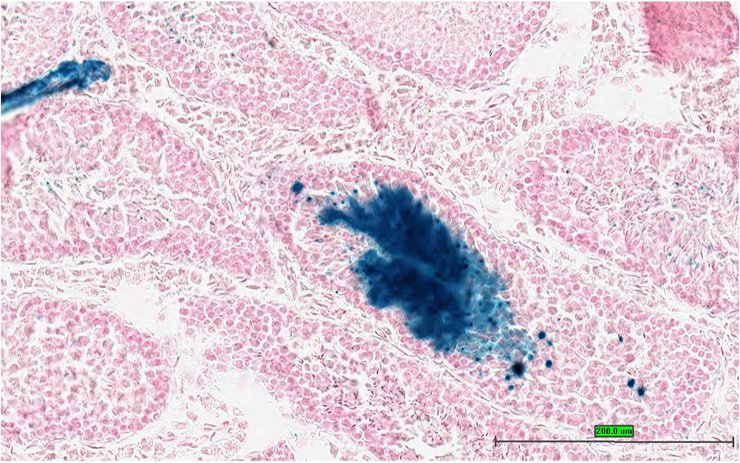

Specimen UC Davis_1866044: postnatal adult; Peli1tm1b(EUCOMM)Wtsi/Peli1+ (more )

Structure Level Pattern Image Note

TS28: thymus Present UC Davis_1866044